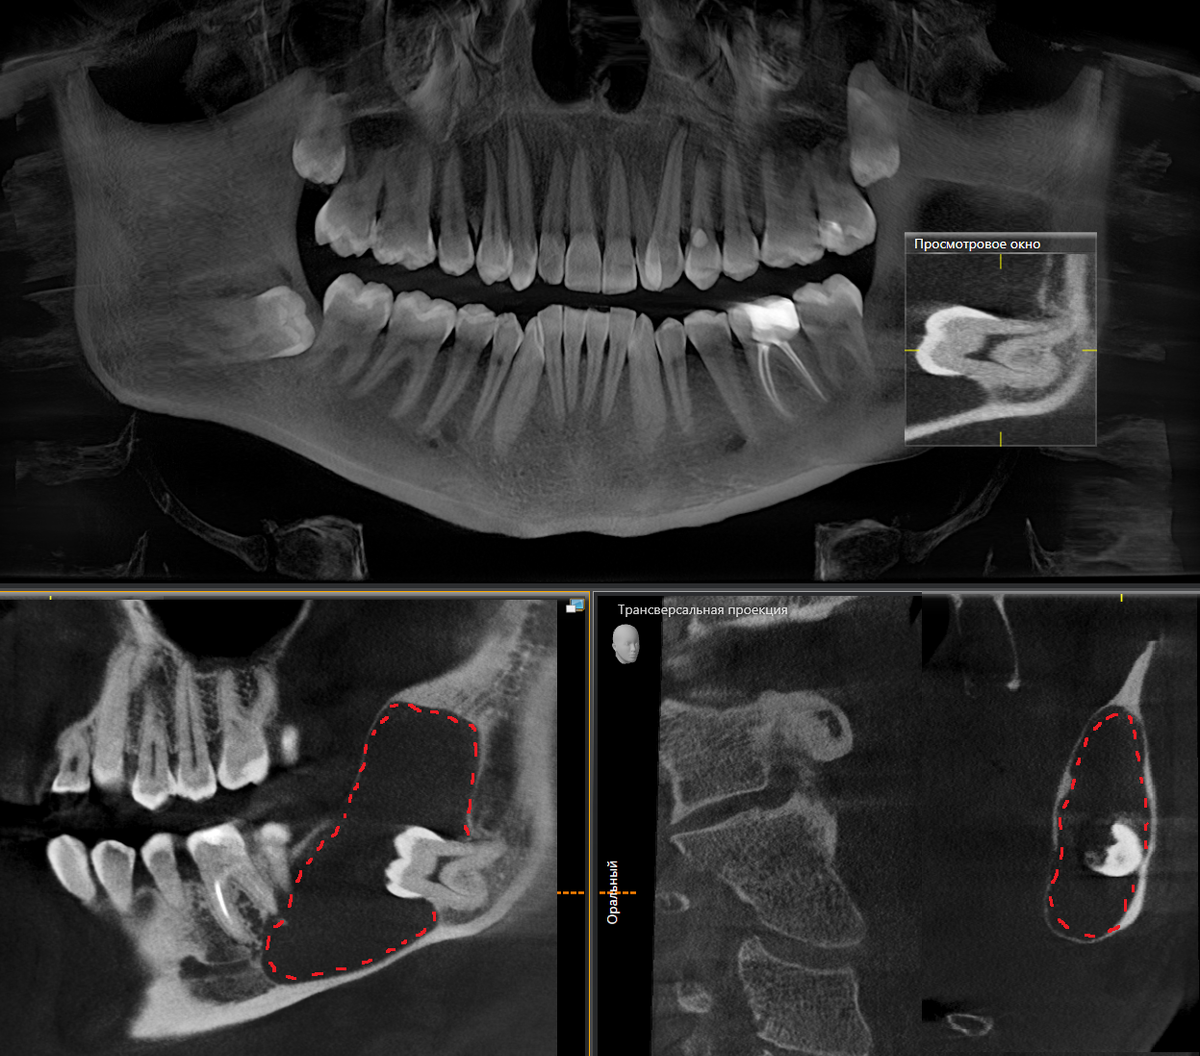

Удаление кисты зуба мудрости

Челюстная киста: симптомы и виды Радикулярная киста, аневризмальная киста и друг